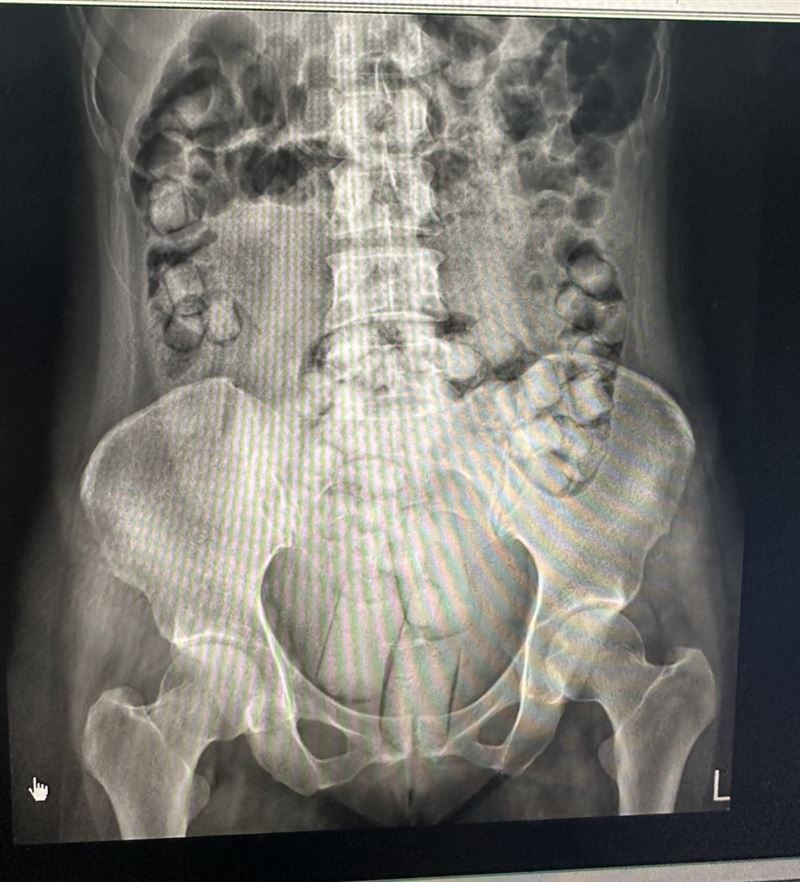

販毒集團先將海洛因毒品分裝在可吞食的橢圓形顆粒,或方便塞入私密處之長條狀,再以保險套或乳膠膜等耐腐蝕性及防水之外袋包裹後,讓2名泰國女子自行加橄欖油吞食及塞入肛門,將毒品夾藏體內規避安檢,鋌而走險從泰國搭機運毒走私來台。

2名泰國女子聲稱,在泰國曼谷透過不知名的泰國人士介紹到台灣旅遊,出發前對方先給了1000元美金,等到順利入境後,會有人打電話聯絡,到時候再約見面交付毒品,給予12萬及8萬酬勞。不料兩人於9月7日一入境台灣小港機場,當場被查出體內夾藏毒品,被帶往醫院排出海洛因毒品,共115顆、重量達664公克。